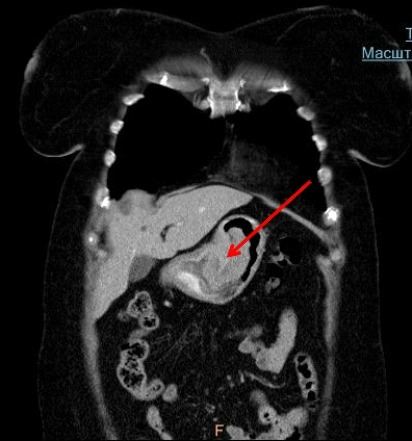

- Компьютерная томография. Дает возможность получить детальнейшие изображения структур желудка. Процедура абсолютно безболезненна и длится не долее 10-15 минут.